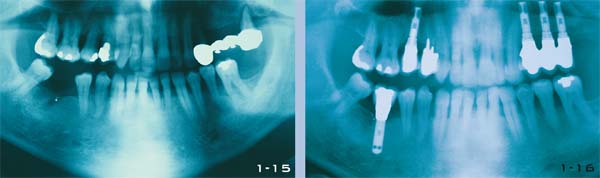

Abb. 1-15 und 1-16 Panoramaaufnahmen eines 75-jährigen Patienten mit Parodontalerkrankung und dem Verlust einiger Seitenzähne; vor und nach der Therapie.

Abb. 1-17 Panoramaaufnahme eines 55-jährigen Mannes, dessen abnehmbare Prothese durch eine festsitzende Versorgung abgelöst werden sollte. Der Behandlungsplan sah vier osseointegrierte schraubenförmige Implantate im Unterkiefer sowie Sinuslift und zylindrische Implantate im Oberkiefer vor.